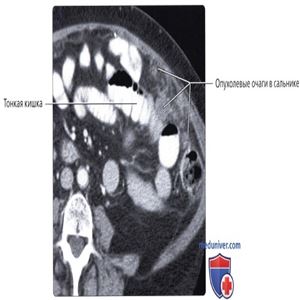

КТ с контрастированием, исследование женщины средних лет с раком яичника, первые два аксиальных среза. В жировой ткани сальника, лежащей выше толстой и тонкой кишок, определяются едва заметные узлы мягкотканной плотности. Эта картина характерна для метастатического поражения брюшины (например, при канцероматозе брюшины).

КТ с контрастированием, аксиальный срез: на этом срезе наиболее четко видны узловые метастазы опухоли в сальнике. Распространение опухоли по брюшине часто, но не всегда сопровождается злокачественным асцитом, в этом случае отсутствующим.